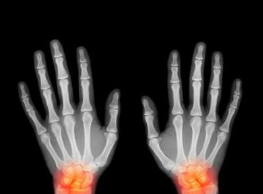

郑州类风湿医院介绍手指得了类风湿性关节炎的患者,一定要在早期及时采取有效的方法进行治疗,而患者使用中药熏洗法治疗非常方便,并且疗效也非常稳定。中医多让患者使用具有祛风散寒以及舒筋活血等作用的药...[详细]